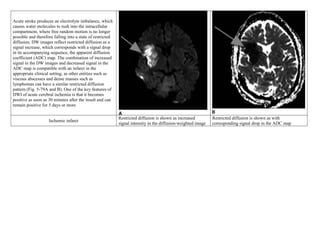

Acute stroke produces an electrolyte imbalance, which

causes water molecules to rush into the intracellular

compartment, where free random motion is no longer

possible and therefore falling into a state of restricted

diffusion. DW images reflect restricted diffusion as a

signal increase, which corresponds with a signal drop

in its accompanying sequence, the apparent diffusion

coefficient (ADC) map. The combination of increased

signal in the DW images and decreased signal in the

ADC map is compatible with an infarct in the

appropriate clinical setting, as other entities such as

viscous abscesses and dense masses such as

lymphomas can have a similar restricted diffusion

pattern (Fig. 5-79A and B). One of the key features of

DWI of acute cerebral ischemia is that it becomes

positive as soon as 30 minutes after the insult and can

remain positive for 5 days or more

Ischemic infarct

Restricted diffusion is shown as increased

signal intensity in the diffusion-weighted image

Restricted diffusion is shown as with

corresponding signal drop in the ADC map